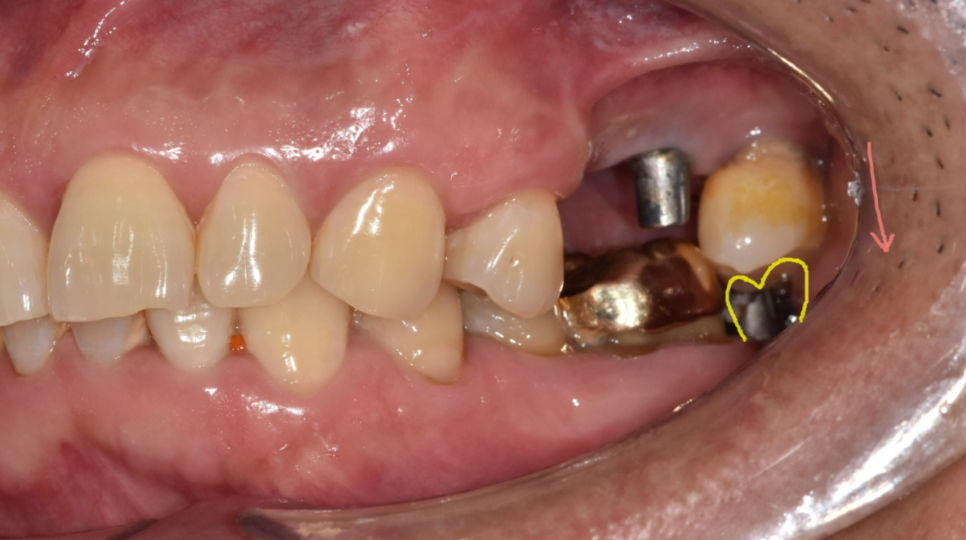

250703 어금니 브릿지 사례

지금도 임플란트 수술이 부담스럽거나

전신질환으로 어려운 경우 여전히 많이 진행되고 있습니다.

브릿지는 수술이 부담스러울 땐

좋은 대안이 될 수 있지만,

옆 치아가 건강할수록 오히려 손해일 수도 있습니다.

건강한 양쪽 치아를 삭제해야한다는 단점이

분명하게 있으니까요.

250703 묶여져 있어 치료도 3개 모두 제거 후 치료해야합니다.

또한 1개 치아에 문제가 생겨도

전체 브릿지를 모두 제거해야한다는 단점이 있고요.